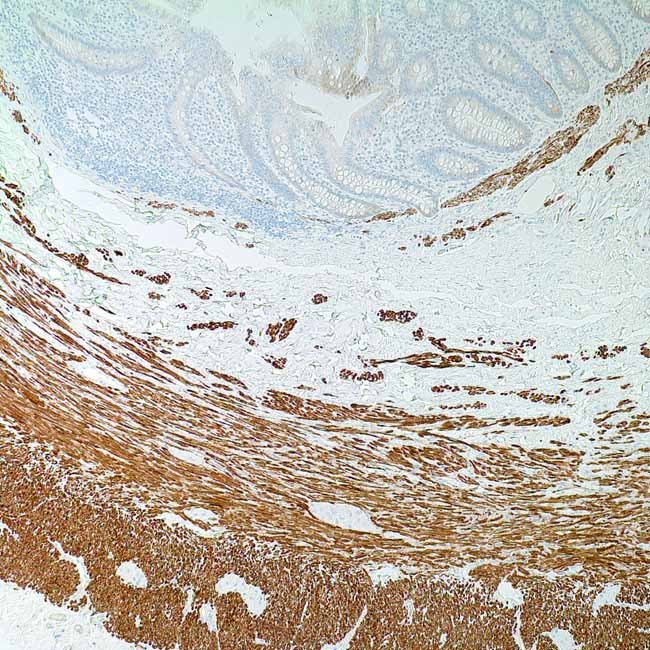

DESMIN (D33)

A 53 kDa intermediate filament protein known as desmin isrecognised by it. According to studies, this MAb exhibits nocross-reaction with other intermediate filament proteinsand is very specific to desmin. Desmin antibody respondswith both smooth and striated muscle cells (cardiac andskeletal). Staining is limited to the Z-bands in cardiac andskeletal muscles, giving them a distinctive striated look.Anti-desmin antibodies are helpful in identifying myogenictumours. It responds to both rhabdomyosarcomas (striatedmuscle) and leiomyosarcomas (smooth muscle).

ControlSkeletal muscle